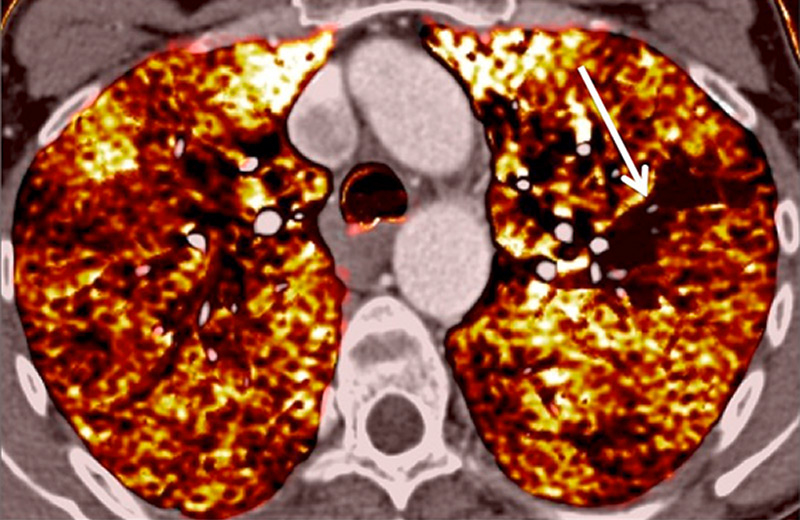

Figure 6

Perfusion heterogeneities in idiopathic pulmonary artery hypertension (stars) in two different patients (A/B). The dilatation of the arteries in pulmonary hypertension (arrows) is not always observed depending on the severity of pulmonary hypertension.